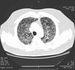

How Would You Treat This Older Patient's Pneumonia?

A 75-year-old man develops fever, chills, and a cough. His history is significant for coronary disease, hypertension, and a 4-cm aortic aneurysm. He has been successfully treated for prostate and colon cancer. He reports that he is allergic to amoxicillin, noting that he developed a rash when taking the drug about 20 years ago. His current medications are atorvastatin, amlodipine, lisinopril, and aspirin.